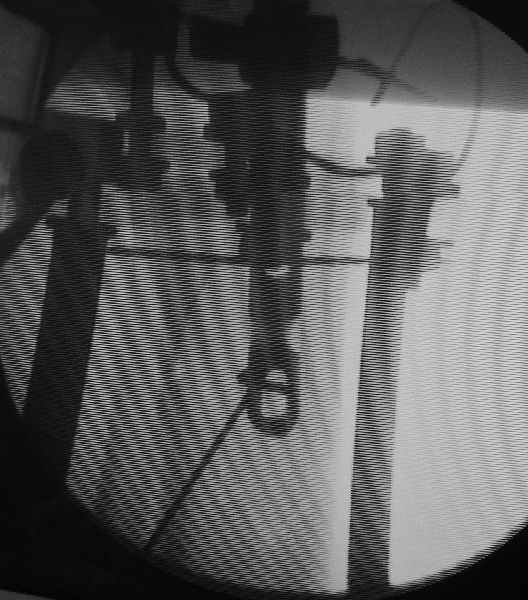

Вот картинка с ЭОП - гвоздь проходит центральный отломок, видно, как спица не дает ему отклониться к задней стенке канала.

|